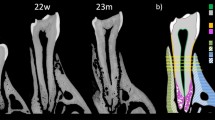

A second and more sophisticated level of study was also achieved, performing the 3D morphometric analysis of the osteocyte lacunae in all the biopsies, as shown in Table 2. Solely for this analysis, data obtained from the two patients involved in peri-dental bone study and from the two patients involved in peri-implant bone study were unified and renamed peri-dental@Test and peri-implant@Test, respectively. Interestingly, standard deviations were quite high, suggesting a repetition of the same investigation, but with a correlation of data to the distance from tooth or titanium implant surface, as shown in Fig. 4. Sampling slices in the peri-dental and in the peri-implant bones were shown in Fig. 4a and in Fig. 4b, respectively. Several subvolumes, approximately 8 × 106 µm3 each, were selected at different distances from tooth/implant surface, namely at 400 µm, 800 µm, 1300 µm and 2000 µm, as shown with the dotted circumference arcs in Fig. 4a,b. Box-plots were used to graphically depict groups of investigated volumes through their quartiles. The distribution of the osteocyte lacunar thickness, volume and density was evaluated in peri-dental (Fig. 4c,e,g) and peri-implant (Fig. 4d,f,h) sites, respectively.

2nd level of study: osteocyte lacunar network. (a-b) Sampling 2D microCT slices: (a) peri-dental bone; (b) peri-implant bone. The histograms have been segmented according to the application of the Mixture Modeling algorithm. Red phase: organic tissues; graded grey phase: mineralized bone. The dotted circumference arcs indicate the different distances of the investigated sites from the tooth/implant surface: namely at 400 µm (*), 800 µm (**), 1300 µm (***) and 2000 µm (****). (T): tooth residual; (I) Implant site, after the implant removing. (c-f) Box-plots graphically depicting groups of investigated volumes at the different distances from the tooth/implant surface through their quartiles: (c-d) osteocyte lacunae thickness (Lac.Th) analysis in peri-dental (c) and peri-implant (d) sites; (e-f) osteocyte lacunae volume (Lac.V) analysis in peri-dental (e) and peri-implant (f) sites; (g-h) osteocyte lacunae density (Lac.Nr) analysis in peri-dental (g) and peri-implant (h) sites.